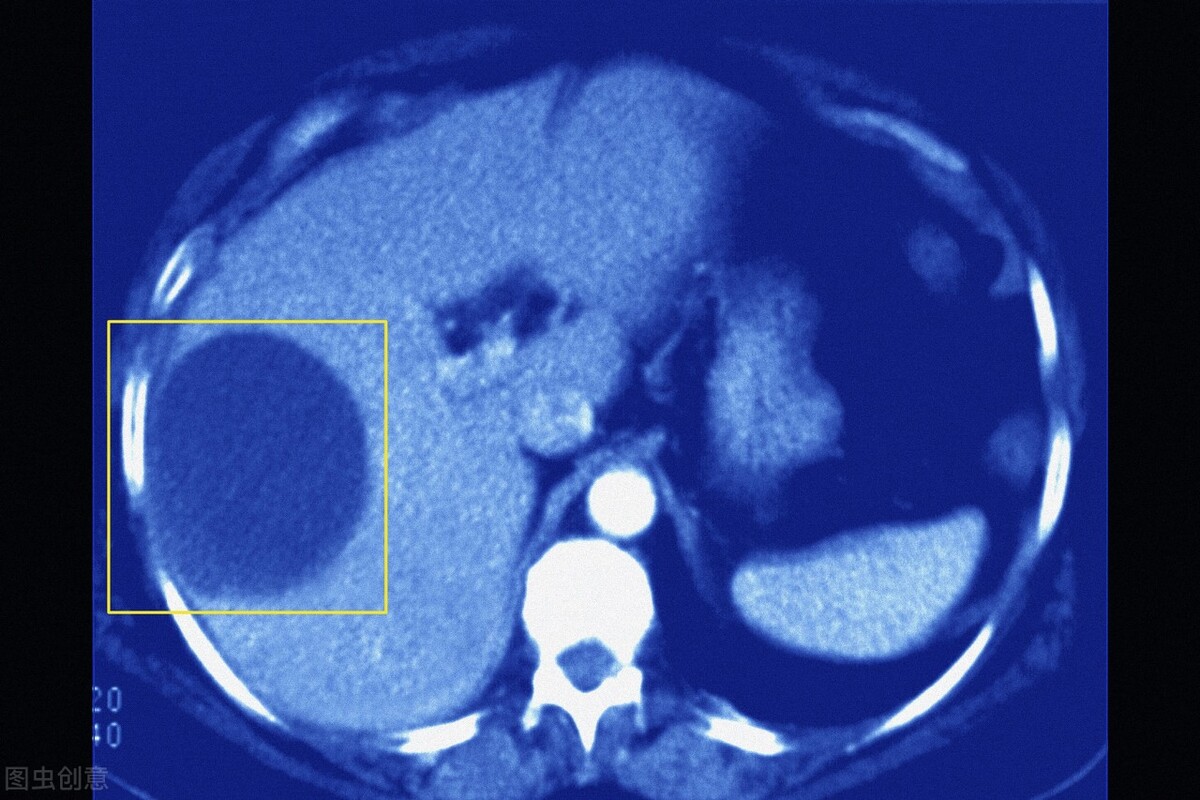

●经过多年的临床实践发现,其实超声是诊断肝囊肿最简便易行的方法, 可作为肝囊肿的诊断依据, 确诊率超过95%。它已有效应用于肝囊肿的筛查, 甚至还可用于胎儿先天性肝囊肿的诊断。有大量的临床实验表明,典型的单纯性囊肿超声图像表现为内部为无回声或仅有少量低水平回声, 囊壁薄, 边缘光滑、整齐, 后壁回声增强。注意了,若囊肿合并感染或出血, 则囊内可出现弥漫性中、低水平回声, 有时底部可有分层现象, 囊壁也可增厚边缘不规则。

●虽说CT、磁共振等影像学检查方法也可显示肝囊肿的结构, 但相比之下, 其实还是超声来得更简单方便、费用低, 也容易被老百姓接受。此外, 超声对肝囊肿的敏感性也很高, 可显示肝内小至2 mm的囊肿,超声还可在对肝囊肿进行定性评价的基础上, 精确地估算囊肿的大小、形态及位置等, 从而对囊肿进行分级,故而这就是我推荐B超检查的理由。